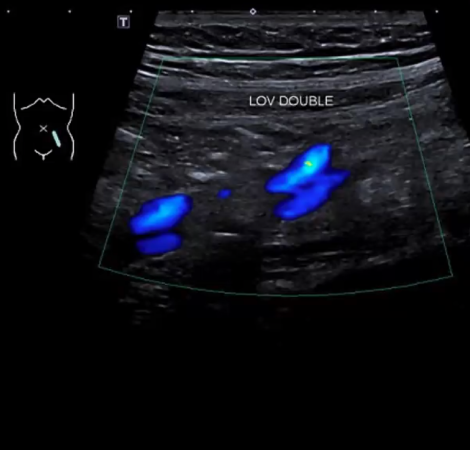

Το ποσοστό των γυναικών που έχουν συμπτώματα πυελικής συμφόρησης μπορεί να αυξηθεί μετά από τη 2η εγκυμοσύνη. Στα γεννητικά όργανα και το περίνεο μπορεί να εμφανιστούν διατεταγμένες φλέβες, κιρσοί και πόνος μη περιόδου στην πύελο, καθώς και αίσθημα συνεχομένου βάρους.

Το σύνδρομο πυελικής συμφόρησης προκαλείται από την ανεπαρκή επαναφορά του φλεβικού συστήματος, αποτελώντας συνέπεια της φλεβικής στασιμότητας. Εξαιτίας της έλλειψης ροής του αίματος στις φλέβες της περιοχής του πελβικού ιστού, όπως στα γεννητικά όργανα, την ουροδόχο κύστη και το έντερο, το αίμα αντιμετωπίζει δυσκολία στην επαναφορά του, προκαλώντας πιθανώς την εμφάνιση κιρσών στα γεννητικά όργα και τα κάτω άκρα.